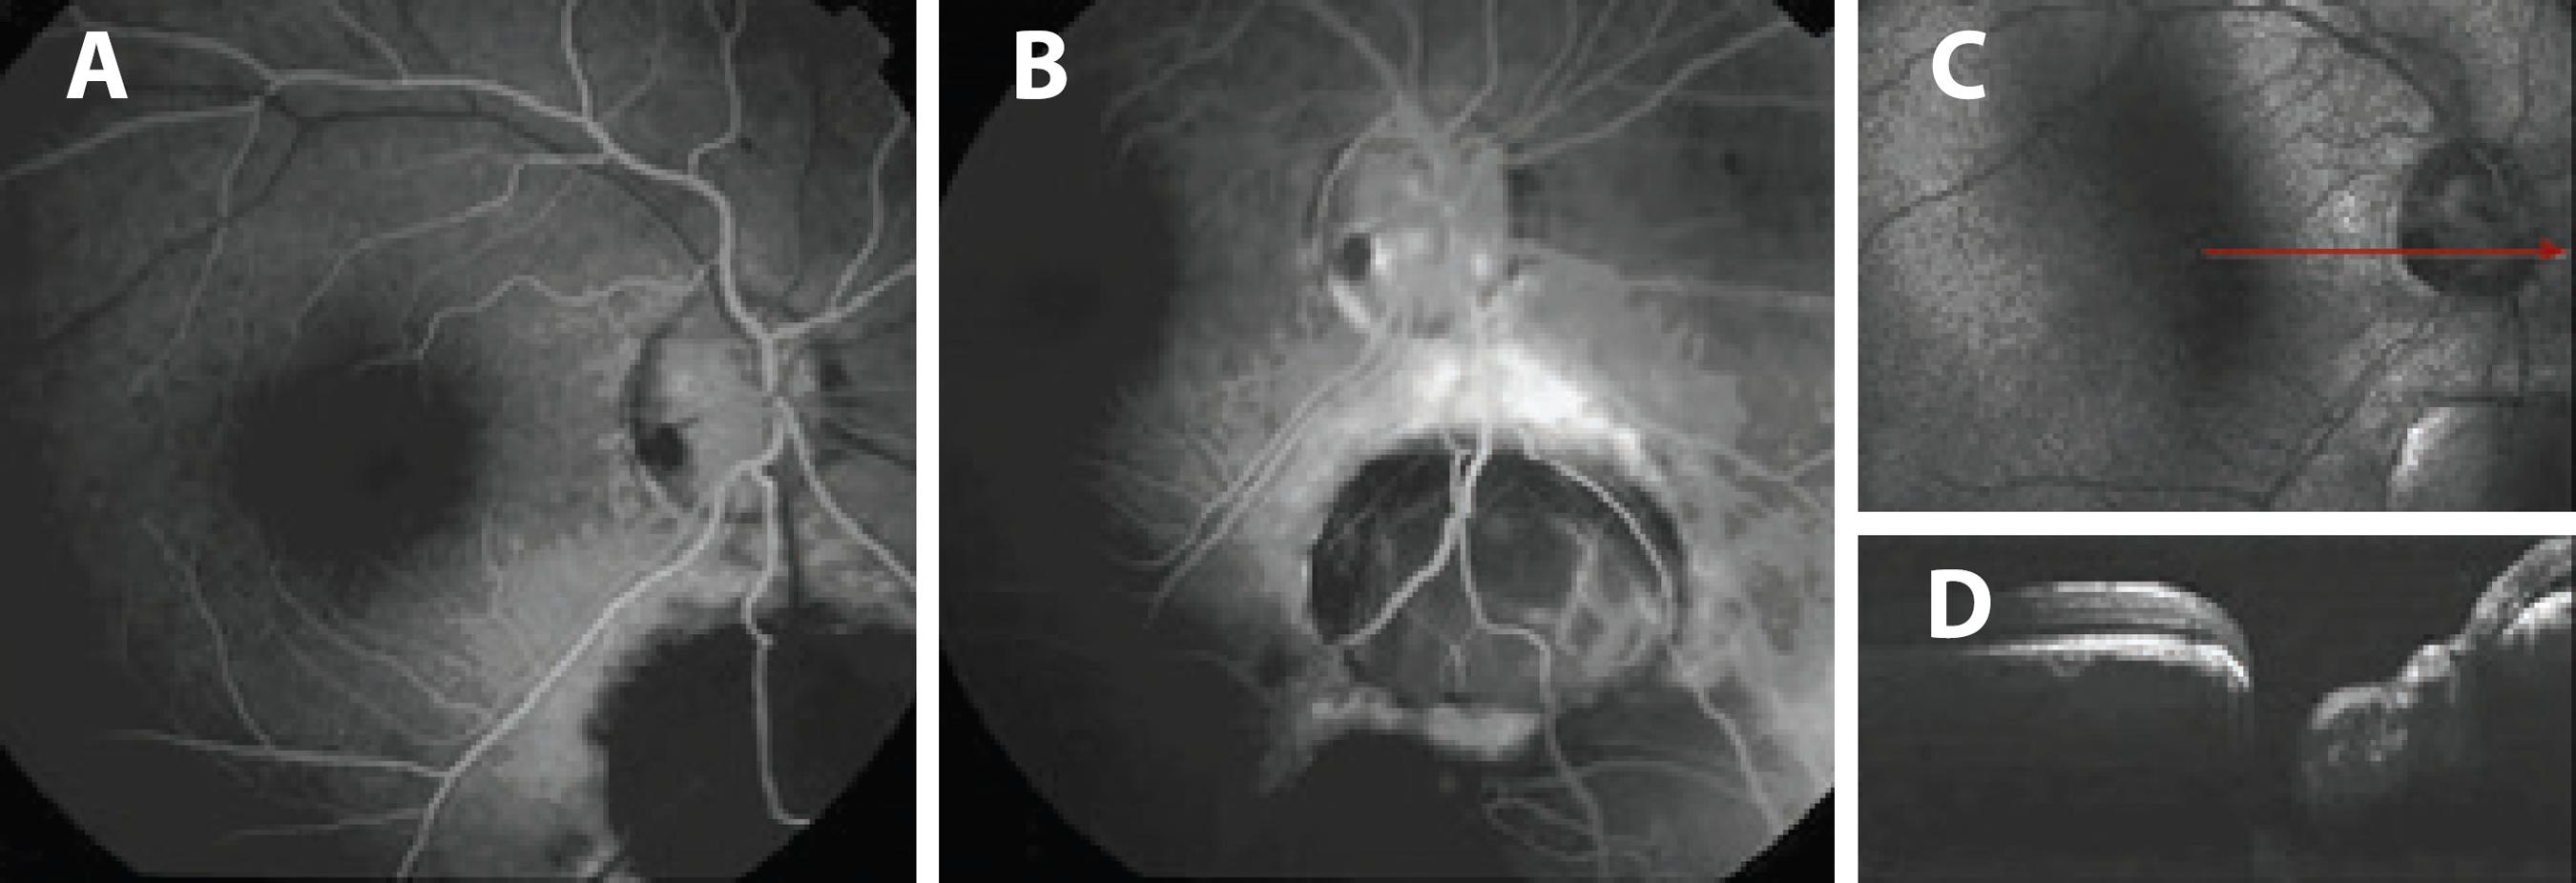

A 42-year-old woman was admitted with a complaint of glare in both the eyes. On ophthalmic examination, her best corrected visual acuity (BCVA) was 20/20 in both the eyes. Biomicroscopic examination of the right eye revealed iris and lens colobomas in the inferior quadrant, pigment precipitates on the lens, and posterior subcapsular cataract (Figure 1 A). In the left eye, there was an iris coloboma in the inferonasal quadrant and iris septa near the limbus that connects the iris tissue, pigment precipitates on the lens, and a lens coloboma in the inferonasal quadrant (Figure 1 B). Bilateral intraocular pressure was 18 mmHg. Fundus examination of the right eye revealed an oval and gray inferotemporal optic pit and two choroid colobomas (one was 2-disc size and an anteriorly located one was 8-disc size, extending to the equator) in the inferior quadrant (Figure 2 A). Under the left optic disc was a 4-disc-sized choroid coloboma that was covered with a membrane with a 1-optic disc-sized hole. A second 7-disc-sized coloboma was detected at the anterior of the coloboma, and pigment alterations were observed around both (Figure 2 B). No retinal detachment was found, and the bilateral maculae were normal. In the right eye, the optic pit revealed hypofluorescence in the early phase and relative hyperfluorescence in the late phase of FFA, as did the bilateral choroid colobomas (Figure 3). Results of optical coherence tomography (OCT) of the optic pit are shown in figures 3 C and 3 D.

Figure 3 A) Hypofluorescent optic pit and choroidal coloboma in the early phase of FFA of the right eye, case 1. B) Relatively hyperfluorescent optic pit and choroidal coloboma in the late phase of FFA of the right eye, case 1. C) Colorless image of the right fundus captured by OCT and a red arrow cross the optic pit, case 1. D) A deep optic pit is seen in the horizontal section of an OCT image of the right eye, case 1.